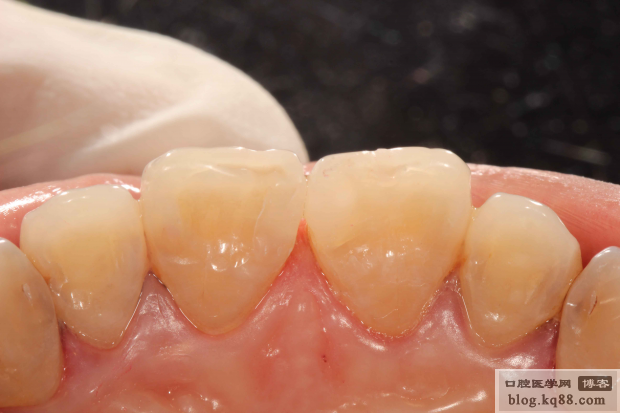

隔日修整初步拋光

隔日高光澤度拋光

隔日高光澤度拋光黑白照